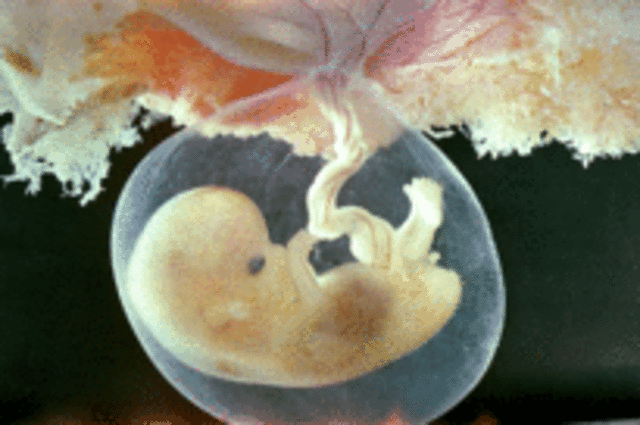

• A magzat fejlődése a második hónapban

A magzat fejlődése a második hónapban

A megtermékenyülést követő 56. napra az embrió szervei nagyjából kialakulnak. Az embrió már képes reflexes mozgásokat is végezni és folyton mozgásban van.